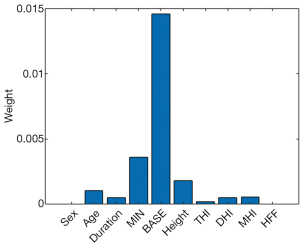

In particular, the RF algorithm (i.e., one of the five algorithms in this study) can be used to evaluate the importance of predictors in a dataset. It estimates the importance of each predictor by using the predictorImportance function in MATLAB. This function sums changes in the mean-squared error due to splits on every predictor and then divides the sum by the number of branch nodes. As a result, the function generates the weight of each predictor and provides a graphical display for assessment.

In the external validation, the AUC obtained by the RF algorithm was 0.940, with an accuracy of 0.875, a sensitivity of 0.875, and a specificity of 0.958 (Table 2 and Figure 3B). Furthermore, our best-performing model (i.e., RF algorithm) identified BASE as the most critical parameter for the accurate prediction of postoperative IMH status (Figure 4). To better illustrate the importance of BASE, binary logistic regression analysis was derived for prediction of IMH status using BASE in internal validation set. The ROC curve of BASE was showed in Figure 5, with an AUC of 0.911.

In addition, our best-performing ML model (using RF algorithm) identified that BASE is the most critical feature for the prediction of postoperative IMH status, and a binary logistic regression analyse derived for BASE also presented a well-performed result, with an AUC of 0.911. These findings suggest that the size of IMH may be the most important parameter to determine the postoperative status. Most investigators have assumed that tangential traction to the fovea plays a crucial role in the development of IMH and that the success of IMH surgery is highly dependent on the relief of such traction. BASE, the maximum diameter of IMH at the RPE layer, directly reflects the size of retinal defects in the foveal neurosensory retina. In addition, it serves as an indicator of the transverse traction force to the fovea. Therefore a smaller BASE often means less tractional force, which is more likely to be removed by a standard VILMP surgery. Similarly, a prior study used a binary logistic regression analysis to evaluate the prognosis predictive power of several OCT parameters (e.g., MIN, BASE, MHI), which also showed that BASE is the strongest indicator in predicting anatomical success after IMH surgery (16).